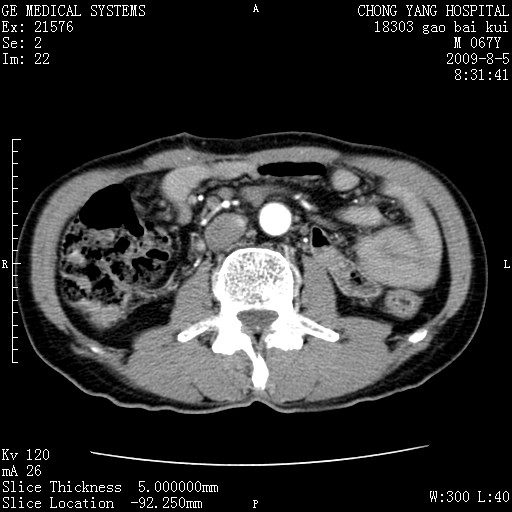

这个也过了,考虑胰腺钩突癌或壶腹癌,不除外胰管粘液乳头瘤伴胰管扩张,肝内胆管积气.

1)考虑胰头癌或壶腹癌并胰管扩张。2)肝外胆管扩张、积气,胆囊影未见;考虑术后改变。3)胃壁增厚?建议必要时行胃镜检查。

考虑胰头癌并十二指肠受侵。